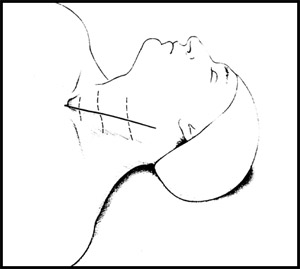

Положение больного лежа на спине. Выполняется разрез на передней поверхности шеи. Мною выполняются косметические разрезы по шейной складе, т.о. после операции у пациента остается едва различимая белая полосочка на коже шеи. (Рис.1) Далее, тупым, бескровным путем достигается передняя поверхность шейного отдела позвоночника. (Рис.2)

| Рис.1. Положение больного на операционном столе. Пунктирной линией обозначено направление кожного разреза. |